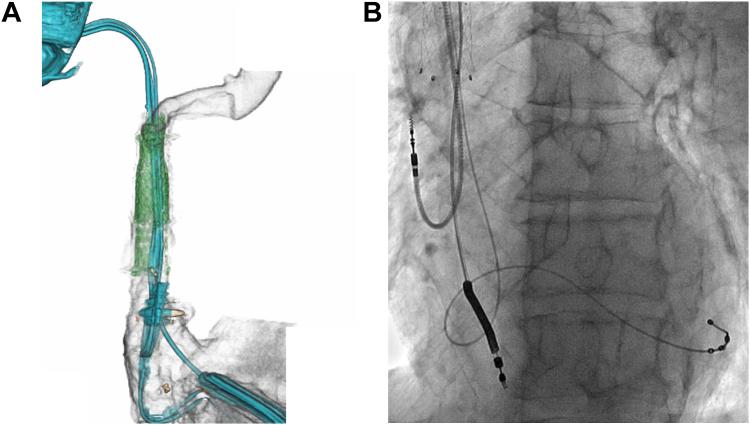

A "one-step" treatment for symptomatic lead-related venous obstruction using percutaneous lead extraction, venous stenting, and new device implantation.

https://cdn.ncbi.nlm.nih.gov/pmc/blobs/34ff/11228062/dddfa2feda03/gr1.jpg